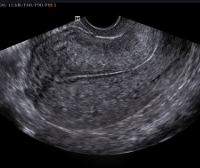

O34.2 Послеоперационный рубец матки, требующий предоставления медицинской помощи матери